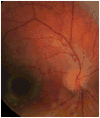

Results: Unresponsive mydriatic pupils with scalloping wisps of persistent pupillary membrane from the iris collarette were an early indicator of this rare genetic disorder in all three cases. Tortuousity of retinal arterioles was the main posterior pole finding, apparent during the first year of life and with a tendency to increase with age. In one case, it progressed to an aneurysmal-like state with breakdown of the blood-retinal barrier.